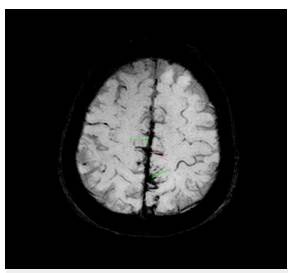

Mujer de 58 años de edad, ama de casa, ingresó por 15 días de evolución de cefalea de inicio hiperagudo pulsátil, en región occipital propagada a región frontal derecha, periorbitaria y nasal, intensidad 9/10, asociado a múltiples emesis, fosfenos y parestesias en manos. Había intensificación con la maniobra de Valsalva, no fue precedida de aura y no tuvo alteración de la conciencia u otro síntoma adicional. Los síntomas se presentaron durante una sesión de masaje en un spa, la paciente relató que en un momento le indicaron que realizara maniobras de Valsalva repetidamente y durante este periodo de tiempo se instaura la cefalea. Como antecedentes, tiene hipertensión arterial y dislipidemia en tratamiento con losartan 50 mg cada día y atorvastatina 40 mg cada noche, negaba abuso de alcohol o de tabaco, y una hija falleció por hemorragia subaracnoidea aneurismática 10 meses atrás. Se encontró deshidratada, con presión arterial 170/80 mmHg, frecuencia cardiaca 82/min; frecuencia respiratoria 20/ min; saturación de oxígeno 92% al ambiente. Talla 1,65 m, peso 78 kg, IMC 28 kg/m2, sin anormalidad en su exámen físico general. En el fondo de ojo se observaron arterias en hilo de cobre bilateral sin papiledema, no tuvo signos de irritación meníngea, no hubo alteración de otros pares craneanos ni de la fuerza o sensibilidad o coordinación. La resonancia cerebral simple mostró sangre en el espacio subaracnoideo de la cisura interhemisférica (Figura 1); dado esto y por el antecedente de la hija, se propuso practicar una panagiografía cerebral. Se trasladó a la unidad de cuidados intermedios y se inició terapia con nimodipino 60 mg cada 4 horas; no presentó deterioro neurológico y el seguimiento con doppler transcraneal no mostró signos de vasoespasmo. En la panangiografía cerebral no se identificaron aneurismas ni malformaciones arteriovenosas o fístulas, sin embargo, en arterias de mediano y pequeño calibre tanto en territorio anterior como posterior se evidenciaron múltiples estenosis y dilataciones segmentarias generando la imagen de "salchichas atadas" (Figuras 2 a 4). Se hizo la solicitud de perfil autoinmune para evaluar dentro del diagnóstico diferencial vasculitis sistémica, los resultados de los anticuerpos fueron: factor reumatoide negativo, C3 146 (normal), C4 28,7 (normal), anticuerpos antimieloperoxidasa negativos, anticuerpos antiproteinasa 3 negativos, anticuerpos antinucleares negativos.

Figura 1: Secuencia de susceptibilidad magnética por resonancia. Muestra contenido hemático en el espacio subaracnoideo.